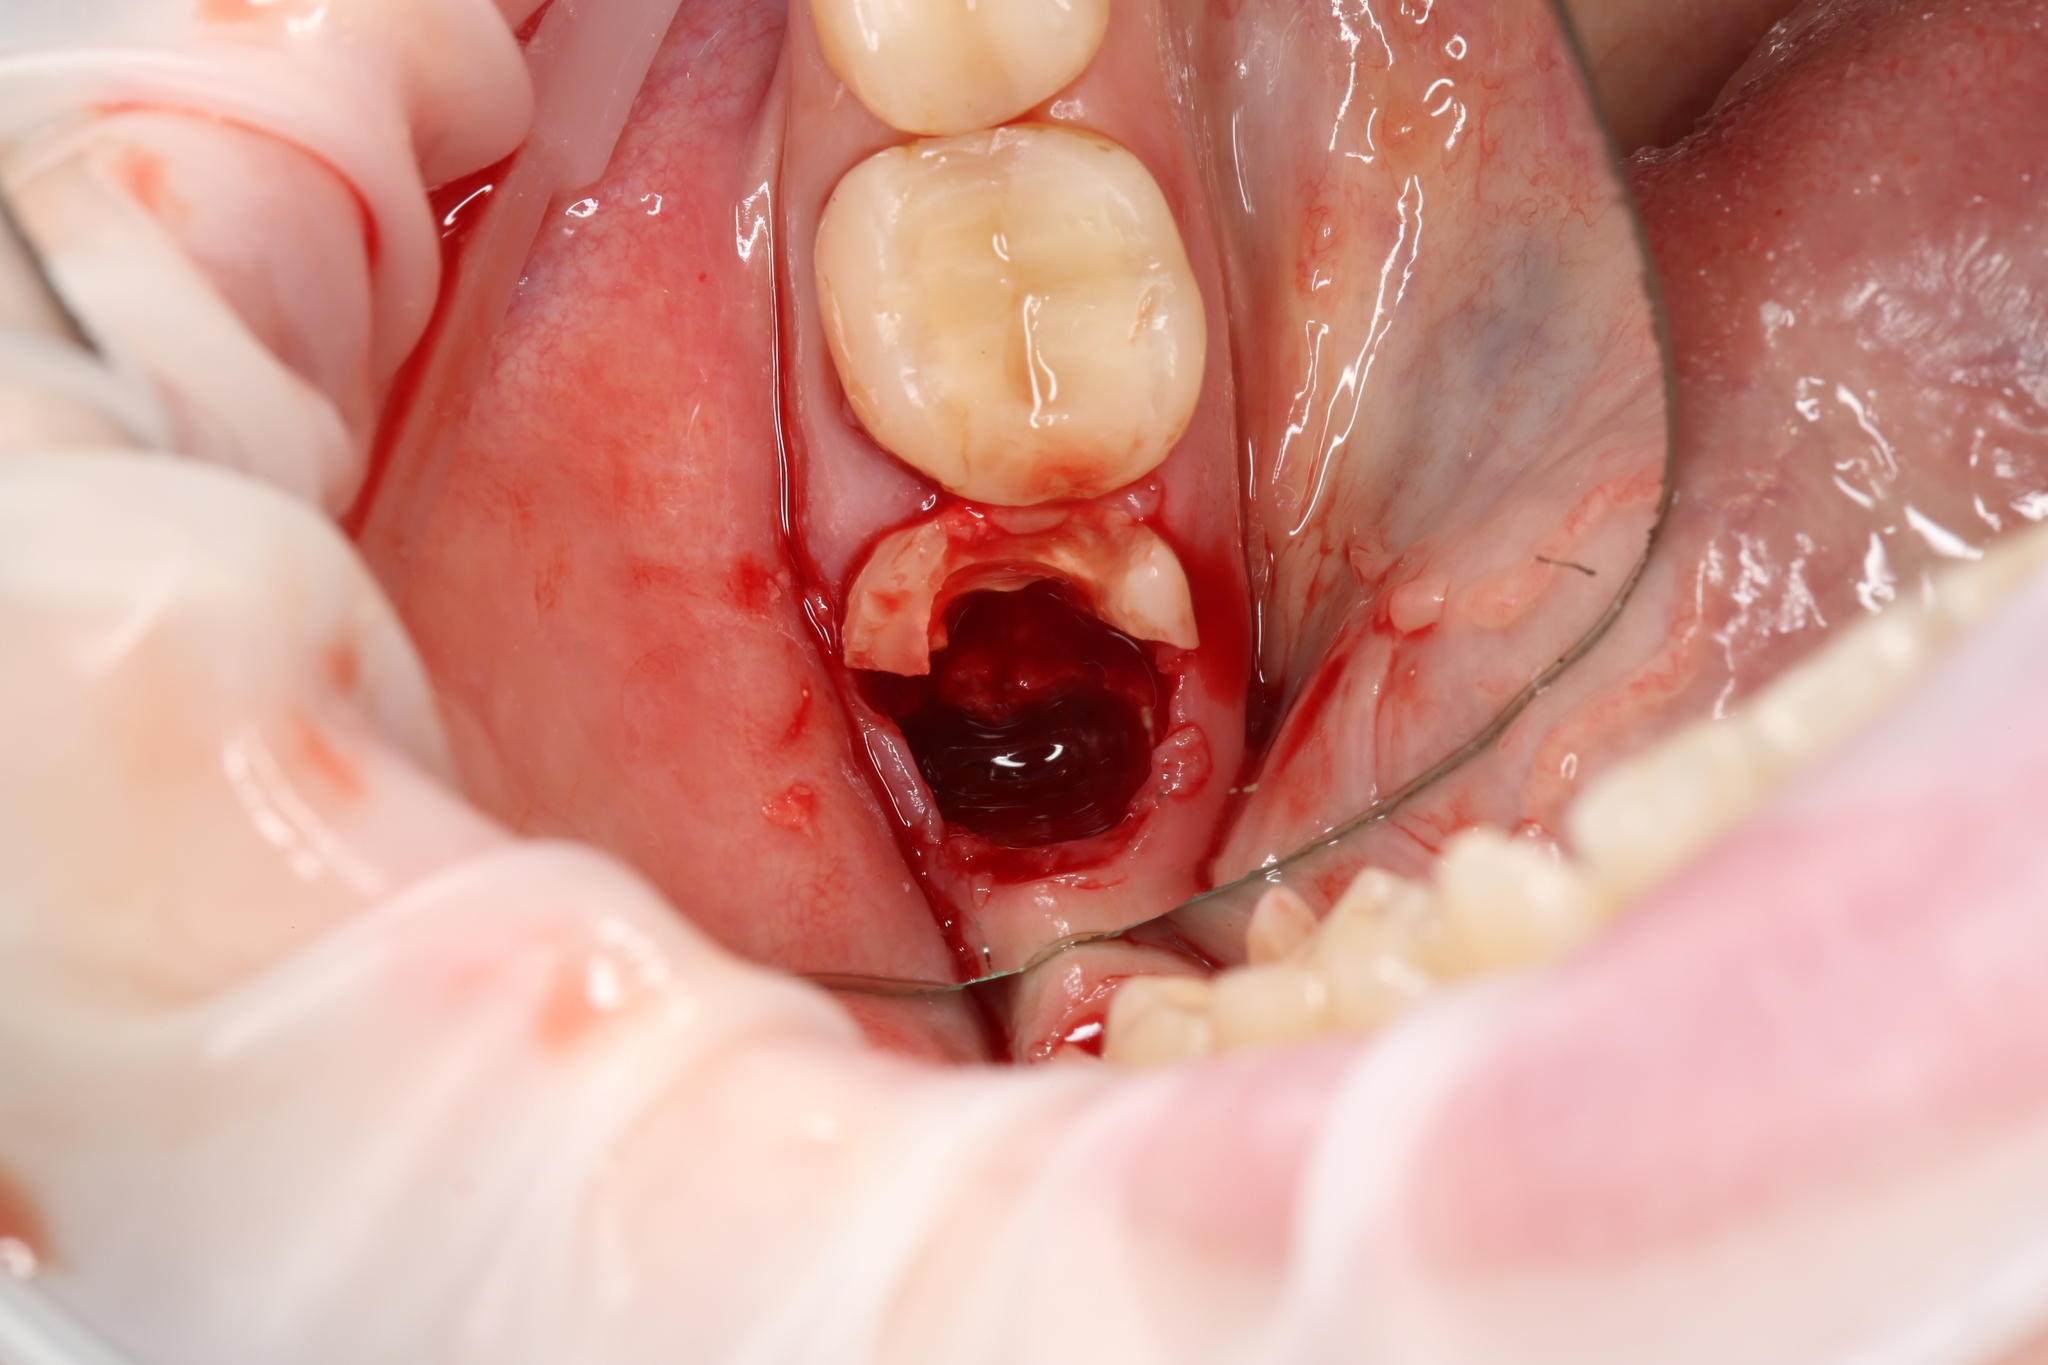

Первым делом при помощи наконечника с охлаждением и бора сносим к херам старую пломбу, да и всю коронковую часть зуба в целом, но (подчеркиваю) делаем это нежно и старательно.

В процессе удаления зуба старая пломба и тонкие стенки все равно сколются, но в наших силах и интересах сделать это аккуратно.

После этого все теми же приблудами нужно отделить каждый из корней зуба друга от друга.

Как мы выяснили, их (корня) три.

Удалили один корень:

Затем второй:

Зачастую последним удаляемым корнем является небный, потому как он самый массивный.

Закончили упражнение:

Вы только посмотрите, какая сочная, крепкая и, что самое главное, целая перегородка. Так и хочется вставить. Имплантат.